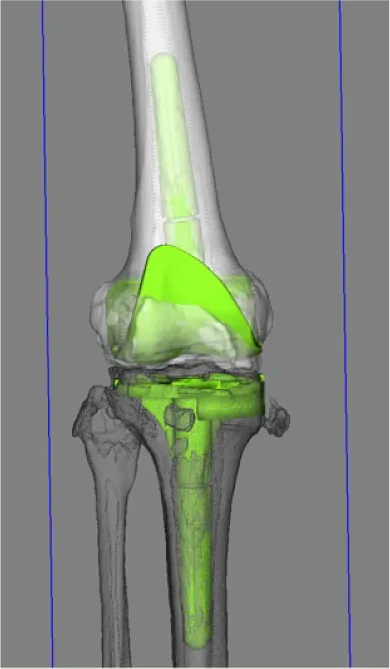

当院では、術後安定して歩ける膝、良好な機能獲得を目標に、個人個人の膝の形態に合わせたオーダーメイドの人工関節手術を行っております。骨の形は立体的に人それぞれ少しずつ異なっており、術後良好な機能を獲得するためには、それぞれの骨の形に合った手術を行うことが理想的です。

当院では術前のCT画像をコンピューターに取り込み、特別なソフトウエアを使用して、手術を受けられる方個々の骨の形に合うように手術前計画を立てています。

さらにその計画を元に正確な手術ができるよう、最新のARポータブルナビゲーションを使用して手術を行っております。

3次元術前計画

• 術前計画